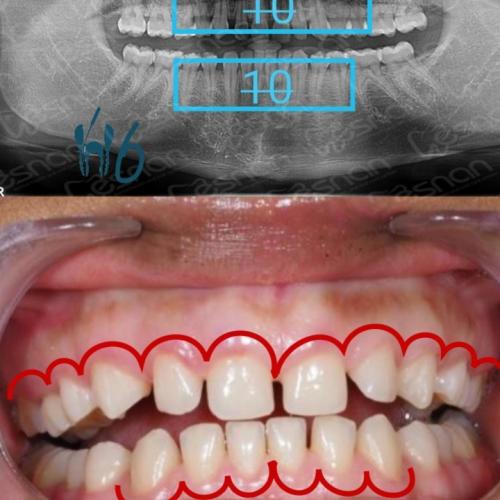

La cirugía ortognática es un procedimiento quirúrgico maxilofacial especializado que corrige las posiciones anómalas de los maxilares. Restablece la armonía facial y optimiza la función masticatoria reposicionando los maxilares.